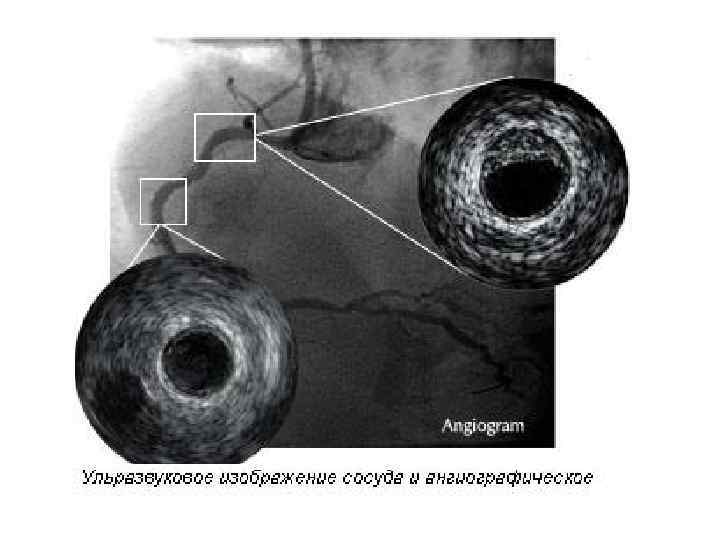

Внутрисосудистое ультразвуковое исследование (ВСУЗИ) • В то время, как ангиография остается золотым стандартом в исследовании коронарных артерий, становится все более и более важным • определение структурных изменений стенки артерии, • а не только степени сужения ее просвета.

Внутрисосудистое ультразвуковое исследование (ВСУЗИ) • В то время, как ангиография остается золотым стандартом в исследовании коронарных артерий, становится все более и более важным • определение структурных изменений стенки артерии, • а не только степени сужения ее просвета.

Коронарограмма пациента с ИБС • а - окклюзия ПМЖВ (стрелка). • б - операция реканализации и стентирование ПМЖВ (стрелка) с полным восстановлением кровотока по этому сосуду. • в - просвет сосуда определяется с помощью внутрисосудистого ультразвука.

Коронарограмма пациента с ИБС • а - окклюзия ПМЖВ (стрелка). • б - операция реканализации и стентирование ПМЖВ (стрелка) с полным восстановлением кровотока по этому сосуду. • в - просвет сосуда определяется с помощью внутрисосудистого ультразвука.